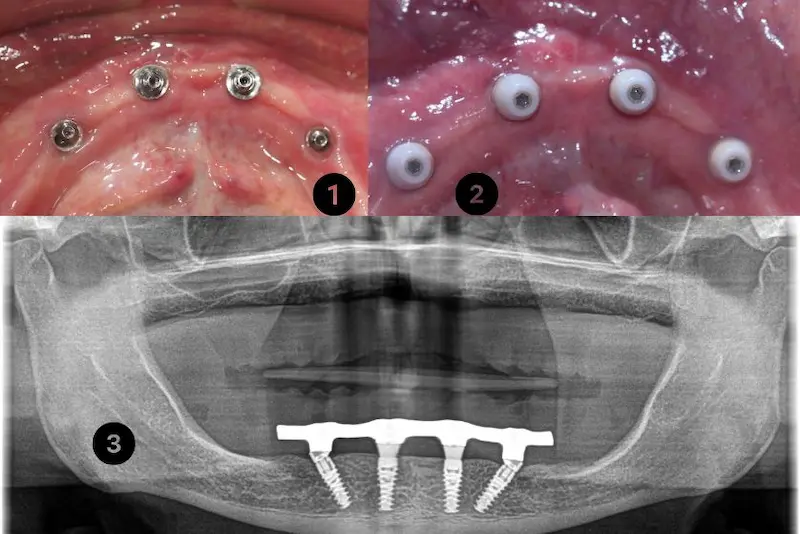

Dental Implants

Restore functionality and aesthetics with our advanced dental implant solutions. Our expert team ensures seamless integration for a natural-looking smile that lasts a lifetime.

Full Mouth Reconstruction

Rejuvenate your oral health with comprehensive full mouth rehabilitation, combining aesthetics and functionality for a complete transformation. Let us craft the smile of your dreams.